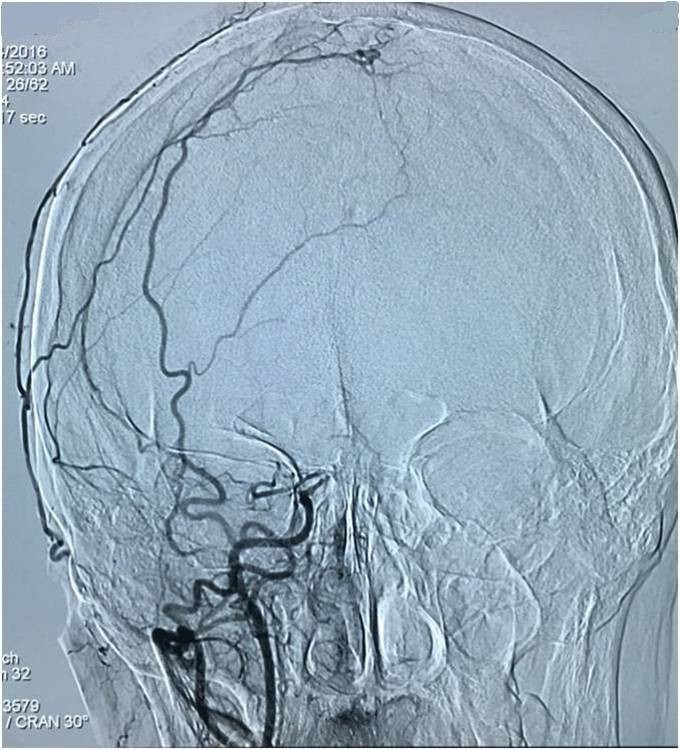

以下图像为DSA,显示基底动脉顶端动脉瘤,左侧小脑上动脉瘤,左侧PCA P1段微小动脉瘤,双侧颈内动脉眼动脉以远闭塞,前循环靠后循环通过后交通动脉代偿。

▼左椎动脉造影正位